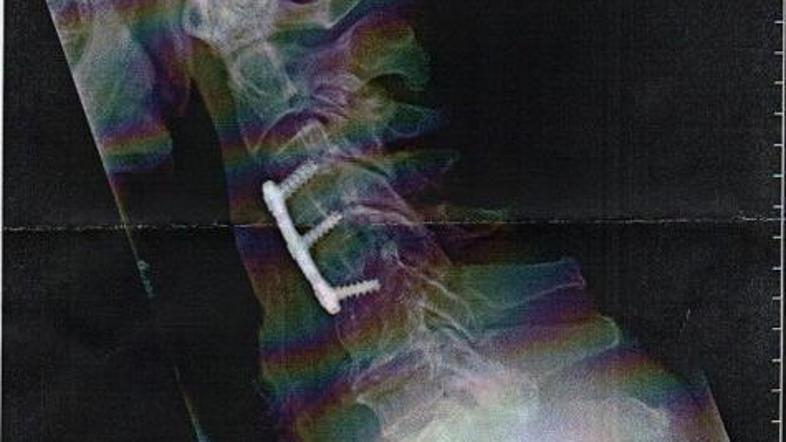

Sylvester Stallone dokazuje, da ne laže. (Foto: StalloneZone) Žurnal24 main

Sylvester Stallone je na spletu objavil rentgenske fotografije zlomljenega vratu, saj mu ljudje niso verjeli, da se je poškodoval.

"Za tiste, ki dvomijo vame, in tiste, ki me sovražijo. Tako, slika je vredna na tisoče besed," je igralec zapisal na svoji uradni spletni strani StalloneZone. 63-letni Sylvester Stallone, ki se ga večina spominja po vlogi Ramba v istoimenskem filmu, je zgrožen, saj nekateri ne verjamejo, da si je na snemanju filma The Expendables zlomil vrat, medtem ko se je boril z nekdanjim ameriškim wrestlerjem, 45-letnim Stevom Austinom

Stallone se je pred kratkim pošalil in dejal, da kljub neznosni bolečini poškodbe ni bilo težko prestati, saj so posneli fantastično sceno. "Ljudje me nikoli niso videli nositi opornico, saj sem bil tri tedne le doma, kjer sem okreval. Ne morem verjeti, da so me označili za lažnivca," je še povedal Stallone.